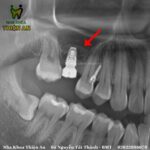

Nâng xoang, ghép xương và trồng 2 implant thay thế răng mất cho c G. (30 tuổi). Tình trạng trước điều trị: vùng xương mất răng hàm trên còn lại ít do mất răng đã lâu, xương tiêu nhiều…

Nâng xoang kín là gì? Là phương pháp tăng chiều cao xương vùng cấy ghép khi xương còn lại quá ít, đây là phương pháp nâng xoang từ bên trong, qua lỗ cấy Implant và không yêu cầu phẫu thuật quá nhiều. Bác sĩ sẽ mở một đường rạch trên nướu đến vùng xoang hàm cần nâng. Sau đó sẽ tạo một lỗ nhỏ ở phần xương để nâng màng xoang lên. Xương hàm cần cấy ghép sau đó sẽ được đưa vào lấp đầy khoảng trống giữa xương hàm và màng xoang mới nâng

Kỹ thuật này ít xâm lấn nên hạn chế sưng đau và đi kèm với quá trình cấy trụ Implant